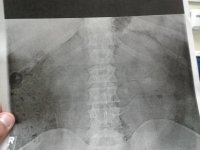

Setting at the hospital had a terrible pain that woke me up found out it is a kidney stone 3 times larger than the last.

View attachment 88581 View attachment 88582